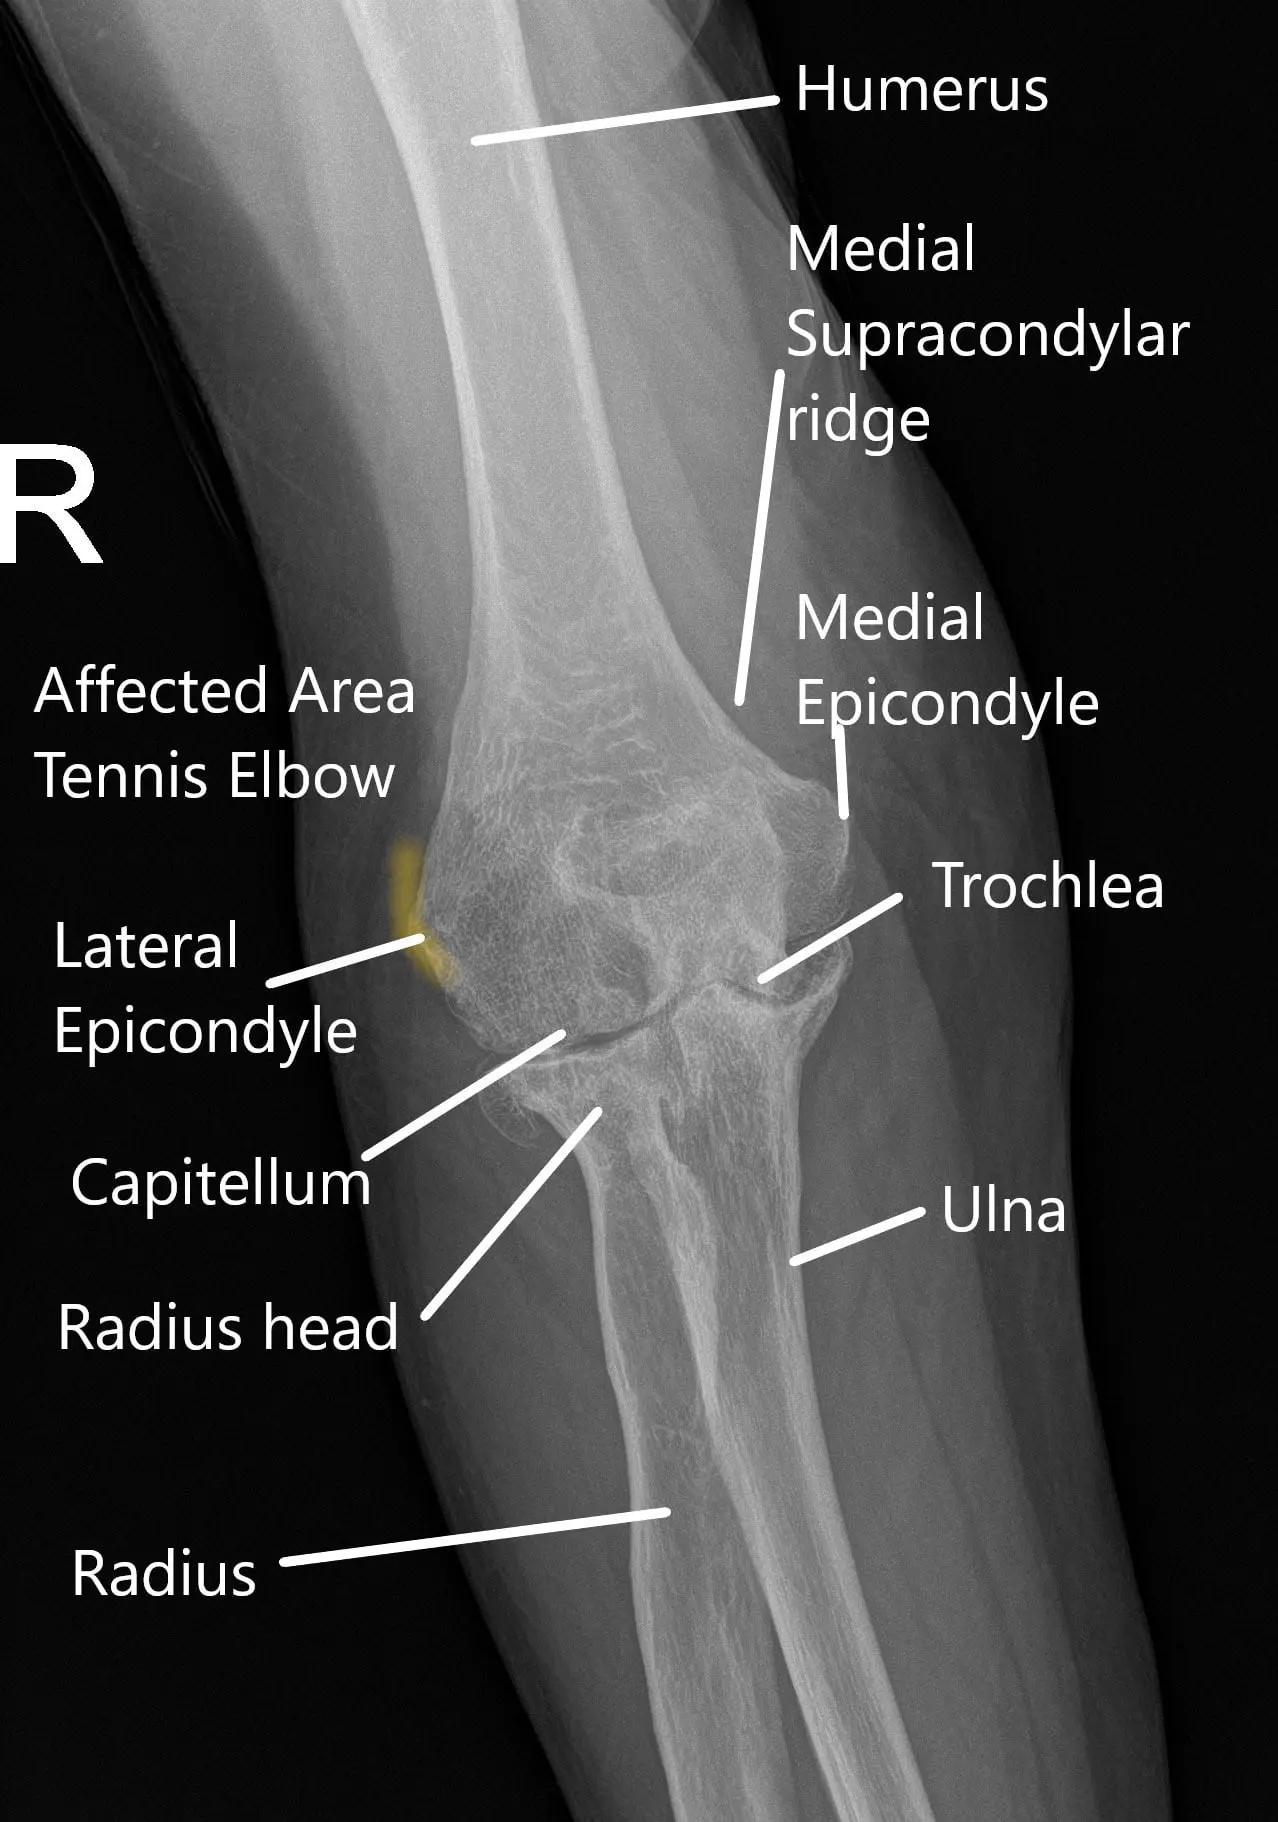

The elbow joint forms between the lower end of the arm bone and the upper end of the two forearm bones. The arm bone is known as the humerus and the two forearm bones as radius and ulna. Various muscles, tendons, and ligaments stabilize the joint. There are small bony bumps on the inner and outer side of the elbow known as epicondyles.

The bump on the outer side is known as the lateral epicondyle. The muscles of the forearm used to straighten the wrist and fingers are attached to the lateral epicondyle. The muscles attach to the bone through tendons.